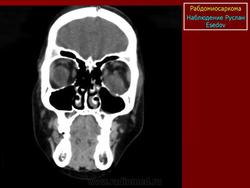

Рабдомиосаркома — чрезвычайно агрессивная опухоль орбиты, является наиболее частой причиной злокачественного роста в орбите у детей. Мальчики болеют почти в 2 раза чаще. Источником роста рабдомиосаркомы являются клетки скелетных мышц. Выделены три типа опухоли: эмбриональный, альвеолярный и плеоморфный, или дифференцированный. Последний тип встречается редко. У детей до 5 лет чаще развивается эмбриональный тип опухоли, после 5 лет — альвеолярный. Как правило, рабдомиосаркома состоит из элементов нескольких типов (смешанный вариант). Точный диагноз можно установить только на основании результатов электронной микроскопии.

Излюбленная локализация опухоли — верхневнутренний квадрант орбиты, поэтому в процесс рано вовлекаются мышца, поднимающая верхнее веко, и верхняя прямая мышца. Птоз, ограничение движений глаза, смещение его книзу и книзу кнутри — это первые признаки, на которые обращают внимание как сами больные, так и окружающие лица. У детей экзофтальм или смещение глаза при локализации опухоли в переднем отделе орбиты развивается в течение нескольких недель (рис. 20.23, а). У взрослых опухоль растет медленнее, в течение нескольких месяцев. Быстрое увеличение экзофтальма сопровождается появлением застойных изменений в эписклеральных венах, глазная щель полностью не смыкается, отмечаются инфильтраты на роговице и ее изъязвление. На глазном дне — застойный диск зрительного нерва. Первично развиваясь вблизи верхневнутренней стенки орбиты, опухоль быстро разрушает прилежащую тонкую костную стенку, прорастает в полость носа, вызывая носовые кровотечения. Ультразвуковое сканирование, компьютерная томография, термография и тонкоигольная аспирационная биопсия — это оптимальный диагностический комплекс инструментальных методов исследования при рабдомиосаркоме (рис. 20.23, б). Лечение комбинированное. Протокол лечения предусматривает предварительное проведение полихимиотерапии в течение 2 нед, после чего проводят наружное облучение орбиты. После комбинированного лечения более 3 лет живут 71 % больных.